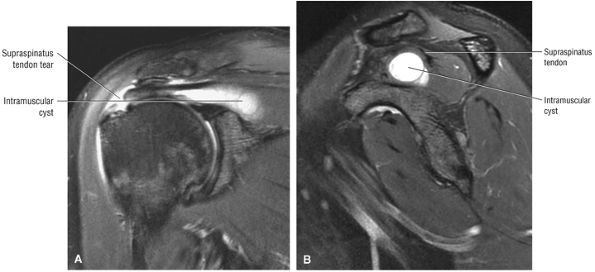

tendon tears and may result from fluid entering the muscle via a one-way valve mechanism through a partial-thickness tendon tear.